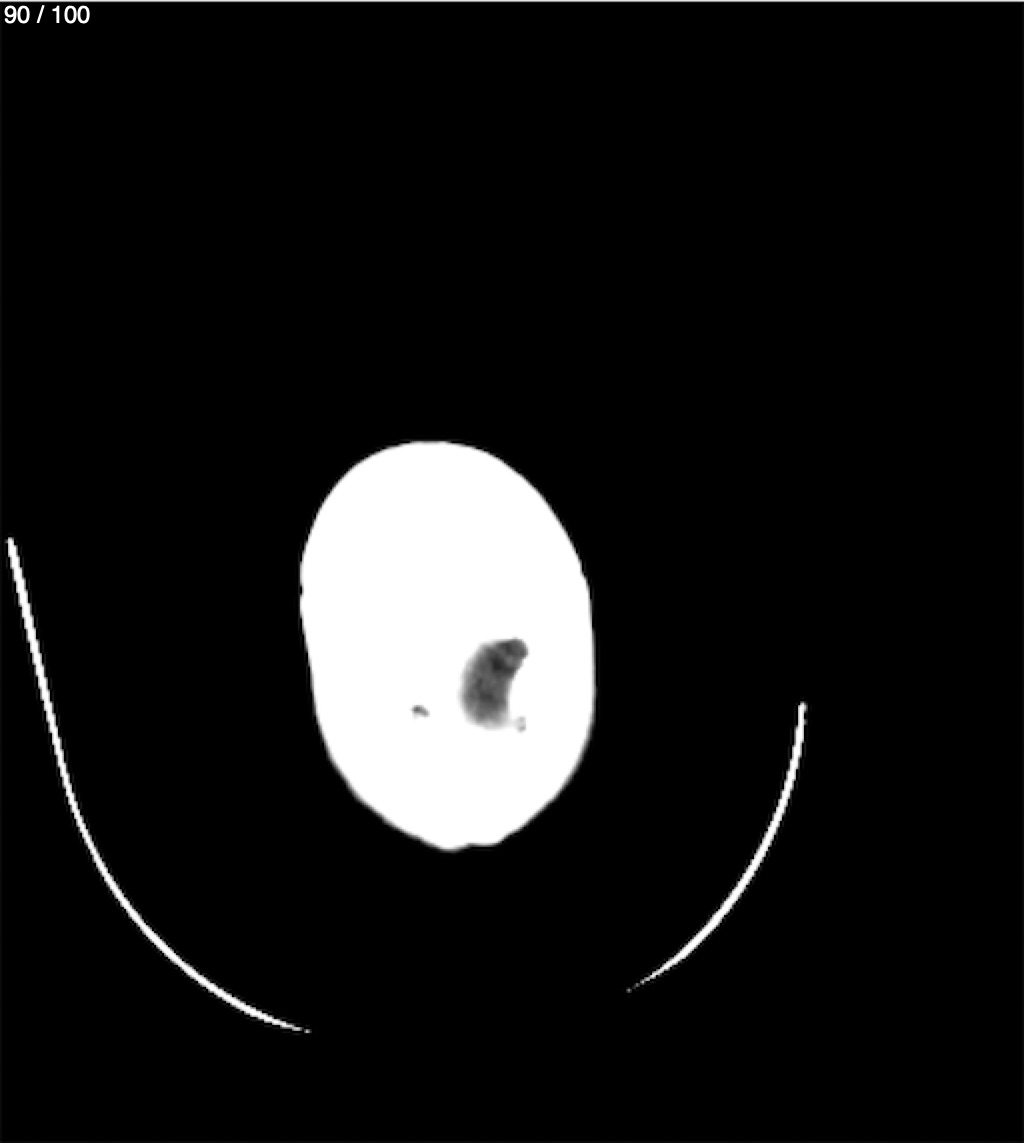

Valentin Perez Gomez 69A - T.C Craneo